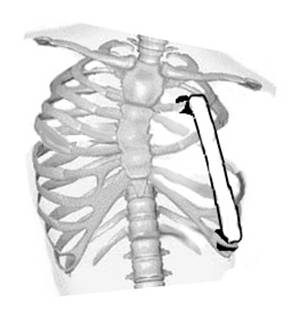

Рис. 7. Фото и рентгенограмма грудной клетки до операции больной К. 3 лет с левосторонним синдромом Поланда и врожденным сколиозом.

1 - аплазия 3, 4, 5 и 6 ребер слева.